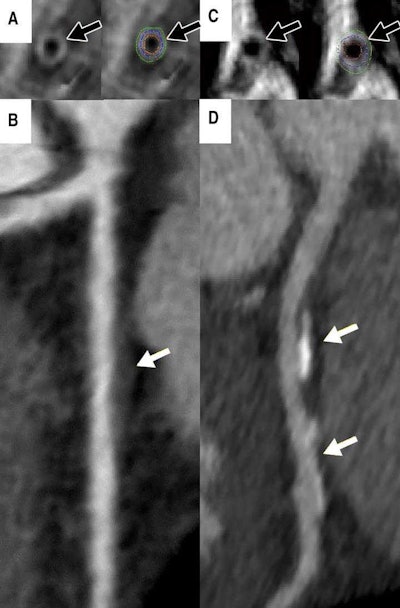

A: Cardiac MRI in a 46-year-old asymptomatic woman shows measured vessel wall thickness of 1.3 mm (black arrows). B: CT angiography shows noncalcified plaque (white arrow) in the proximal left anterior descending coronary artery. C: Cardiac MRI in a 44-year-old asymptomatic woman shows thicker coronary vessel wall (black arrows). D: CT angiography shows coronary artery disease (white arrows). Courtesy of the Radiological Society of North America.The fact that MRI of vessel wall thickness proved to be a strong independent factor of heart disease in young women is a promising study finding that could positively influence patient care, the team noted.